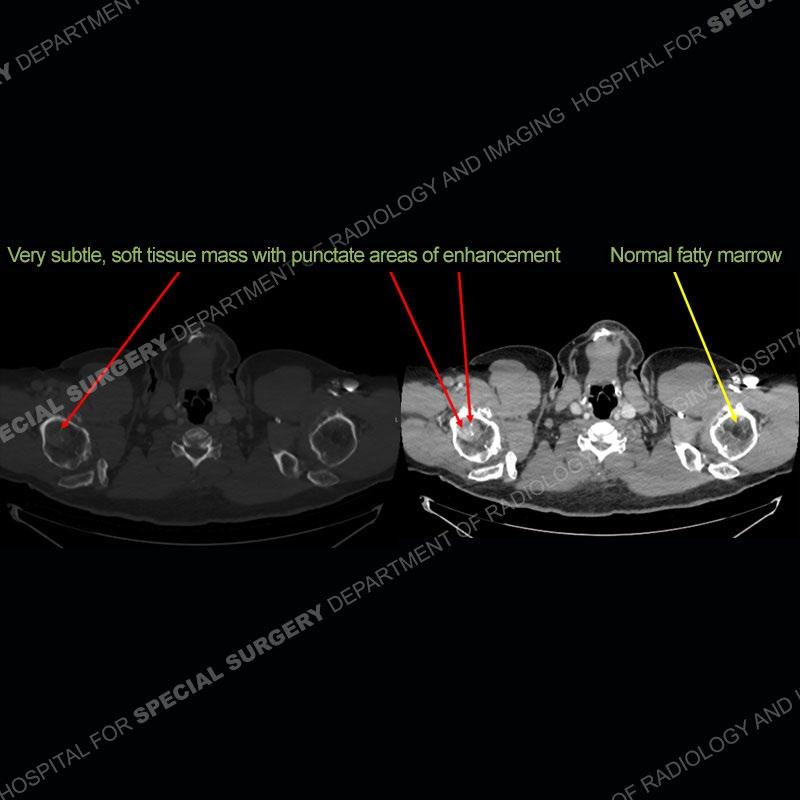

The chest radiographs demonstrate a leftward deviation of the trachea. CT images demonstrate a large, somewhat heterogeneous mass of the thyroid that extends outside the confines of the thyroid tissue. There is a subtle, enhancing soft tissue mass of the proximal right humerus. Slightly prominent mediastinal lymph nodes are present with additionally, multiple supraclavicular lymph nodes.

Although not strictly a part of the evaluation of an “incidental” thyroid lesion, evaluation of the adjacent lymph nodes and bony structures can also be quite important. In this case, there is an enhancing mass of the right humerus. This is very subtle and can only really be recognized by evaluating the density of the bone. Typicaly marrow will have a fatty density or nearly fluid density. As the density, as in this case, approaches soft tissue an infiltrative process must be entertained. Thyroid mets are markedly vascular accounting for the areas of enhancement of the humeral mass. The mediastinal and supraclavicular lymph nodes although not individually enlarged, should raise suspicion of an underlying inflammatory/neoplastic process.